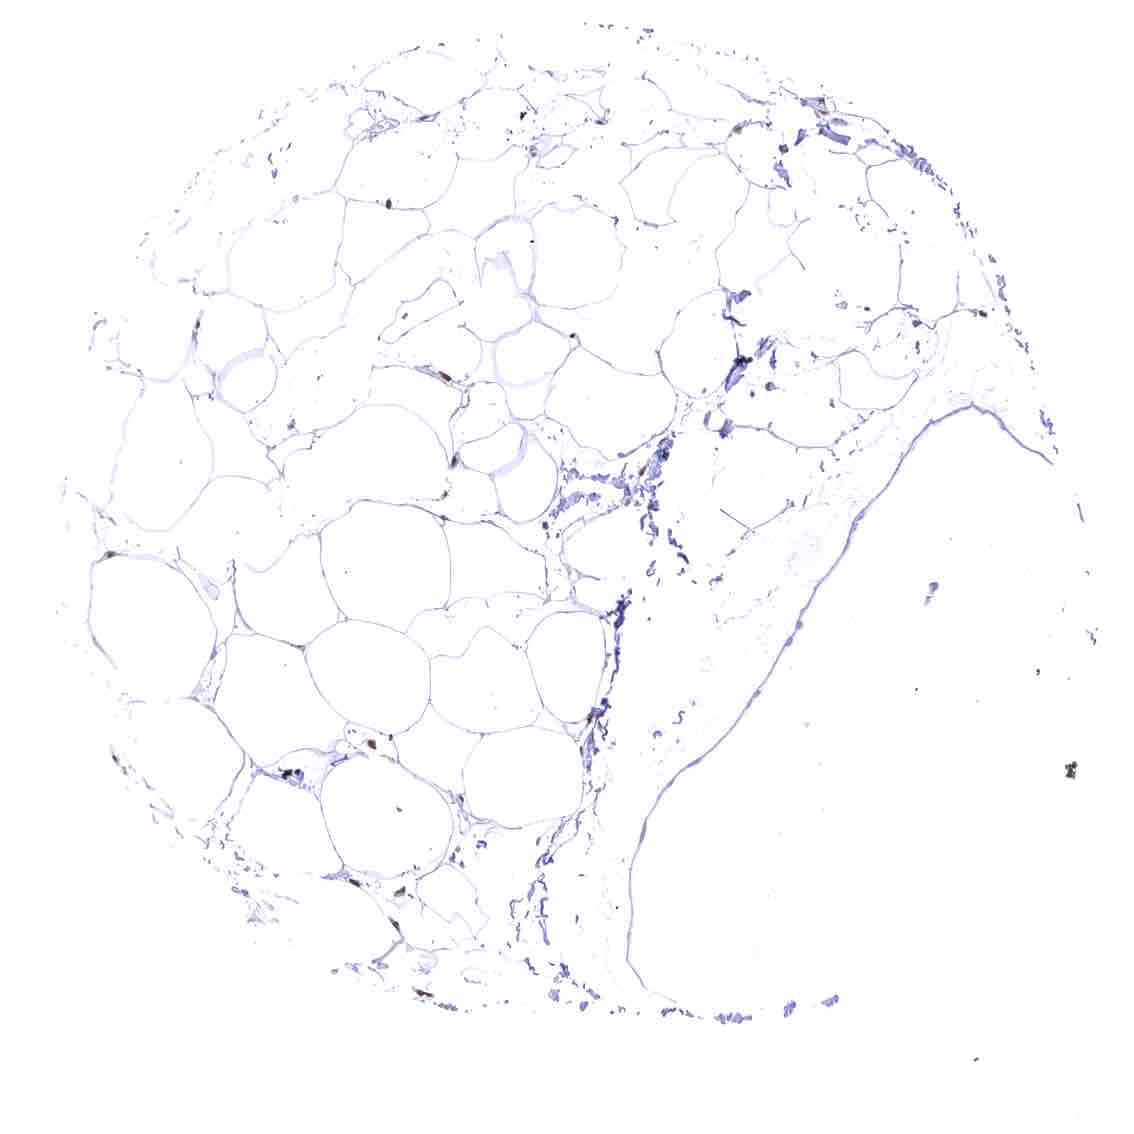

Fat – Variable nuclear p27 staining of at least a fraction of fat cells.